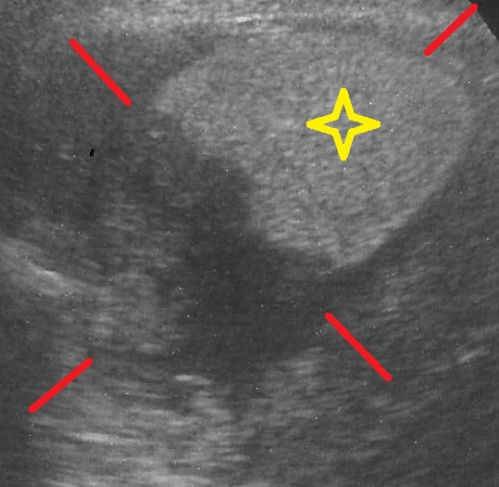

胆泥症の診断は超音波検査によって行われます。典型的な胆泥は画像上で黒く抜けて見える正常な胆汁を背景に胆嚢内を「半月状や不整形」に占拠するような見え方をするのが特徴です。また、また超音波プローブの動きや患者さんの姿勢変化で胆嚢内を緩やかに流動して沈殿するような見え方を特徴とします。

(下図で赤い線に囲まれた黒い円が胆嚢です。胆泥は黄色星印で示しています。)